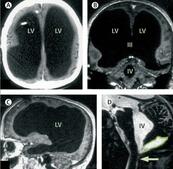

44-годишен французин посетил болница, след като усетил слабост в крака си. Лекарите направили изненадващо откритие: почти целият му мозък липсвал. Черепът му бил запълнен почти изцяло с течност, като от мозъчната тъкан бил останал само тънък слой...